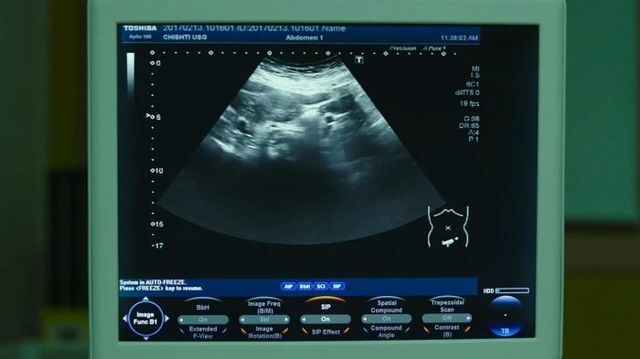

在文馨做B超的时候,多俊耐不住好奇,小心的凑了上去,清楚的看到屏幕上模糊的轮廓。

林多俊那是什么啊?

医生那是您和太太的宝宝啊。

医生也没有轻视林多俊现在的状况,而是温和的向对方耐心解释。

文馨多俊你看,这就是我们的孩子。

林多俊孩子?

文馨对啊,我现在的肚子里有一个属于你和我的小宝宝,等他长大出来了就可以和你一起玩了,你期不期待呀?